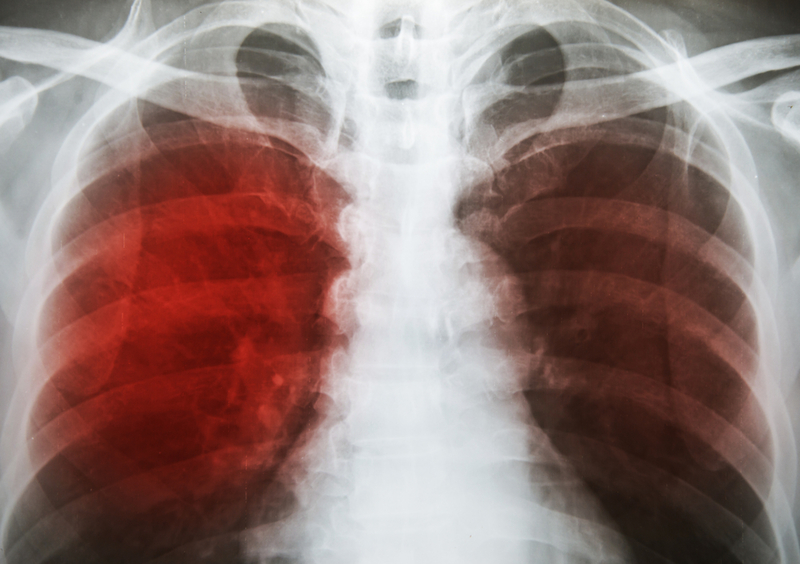

66 Mumbai TB hospital staffers contracted disease in 5 years: RTI

Sixty-six staffers at the Tuberculosis Hospital in Sewri here contracted the disease in the last five years, authorities said in reply to an RTI plea.

Of these 66 employees, 17 had died, 39 had got cured and 10 were still undergoing treatment, the reply by Sewri TB Hospital medical superintendent Dr Lalit Anande stated. The reply revealed that, between 2013-2018, 49 labourers, 11 nurses, two doctors, and one lab technician, radiographer, pharmacist and official each had contracted the disease. The reply pointed out that 2013 was the severest year in this connection with 32 staffers contracting tuberculosis and 10 dying from it.